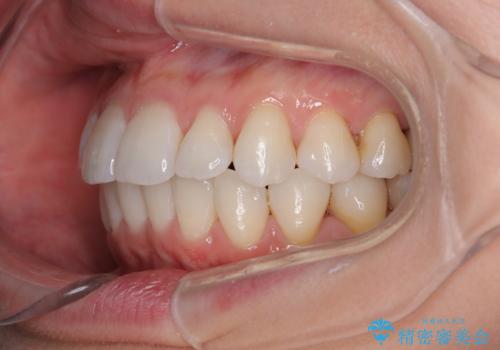

上下前歯のデコボコ ワイヤー装置で楽ちん矯正治療

- 前歯のデコボコや、やや突出した感じを気にして来院された患者様です。

抜歯矯正を必要とするほど口元の突出感はなく、本人もそこまでは気にしていない様子でした。

お仕事柄、マウスピース装着は困難とのことで、表側のワイヤー矯正にて治療を行うこととしました。

デコボコ解消の際に、前歯が前突するリスクがあったため、舌突出癖の改善と、アンカースクリューによる加強固定を行うこととしました。

矯正治療後には奥歯の銀歯やむし歯をセラミックやゴールドにて治療を行い、大変整った口腔環境へと改善さ。れました